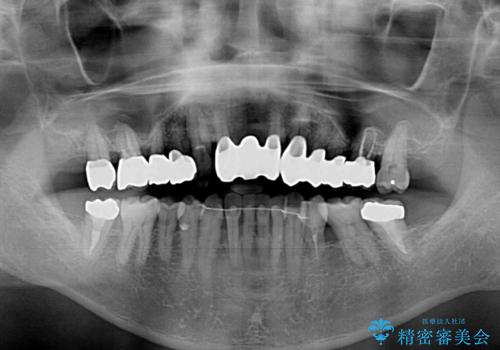

上の歯は見た目を良くしたいというご希望があったため、歯周外科処置を行った歯についてはセラミッククラウンで補綴することとしました。

また、前歯の部分矯正も希望されたため、歯周外科処置と平行して矯正治療を行うこととしました。

気になっていた歯の痛みや歯肉からの出血がなくなり、改善したいと思っていた外見も綺麗に仕上がり、大変満足していただきました。